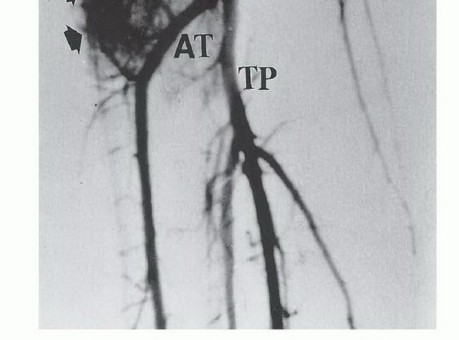

تفرع الشريان المأبضي

يتفرع الشريان المأبضي إلى الشريان الظنبوبي الأمامي، والشريان الظنبوبي الخلفي، والشريان الشظوي عند الحافة السفلية للعضلة المأبضية. يتكون هذا التفرع في الواقع من تفرعين: الأول حيث ينشأ الشريان الظنبوبي الأمامي من الشريان المأبضي، الذي يستمر بعد ذلك كجذع ظنبوبي شظوي. أما التفرع الثاني فيوجد حيث ينشأ الشريان الشظوي والشريان الظنبوبي الخلفي من الجذع الظنبوبي الشظوي، أي أنه يقع بعيداً عن الشريان الظنبوبي الأمامي.

من الضروري تقريباً ربط الشريان الظنبوبي الأمامي أثناء الاستئصال، بينما يجب تحديد الأوعية الأخرى بعناية قبل ربطها. تتميز العضلة المأبضية بكونها تغطي السطح الخلفي لقصبة الساق، مما يوفر حاجزاً ممتازاً بين امتداد الأنسجة الرخوة الخلفية من قصبة الساق والحزمة الوعائية العصبية للطرف السفلي. هذه الميزة التشريحية الفريدة والمحظوظة تختلف عما يحدث في عظم الفخذ البعيد، حيث يتم تغطية الجانب الخلفي فقط بالدهون المأبضية.

يُستخدم تصوير الأوعية ثنائي المستوى (Angiography) لتقييم الشرايين المحلية، خاصة إذا كشف التصوير المقطعي المحوسب عن امتداد الورم إلى الأنسجة الرخوة الخلفية. تُستخدم الرؤية الأمامية الخلفية لتقييم تفرع الشريان المأبضي، مع التركيز بشكل خاص على سلامة الشريان الظنبوبي الخلفي، والذي قد يكون المصدر الوحيد لإمداد الدم للساق بعد الاستئصال.

تُعد الرؤية الجانبية ضرورية لتقييم المسافة بين قصبة الساق والحزمة الوعائية العصبية. على سبيل المثال، غالباً ما تفصل العضلة المأبضية كتلة الورم الخلفية عن الأوعية الدموية. ينعكس هذا كمسافة واضحة في تصوير الأوعية الجانبي، ويشير إلى وجود هامش استئصال كافٍ. غالباً ما يكون ربط الشريان الظنبوبي الأمامي ضرورياً. قد يتأثر الشريان الشظوي بالأورام التي تشغل حجرة خلفية كبيرة. في المرضى الشباب، يمكن ربط اثنين من الأوعية الرئيسية دون تعريض إمكانية بقاء الطرف حياً وظيفياً للخطر. نادراً ما يتأثر الشريان الظنبوبي الخلفي بالورم.

صورة توضيحية للشريان المأبضي.

صورة وعائية جانبية للشريان المأبضي تظهر المسافة بين الورم والحزمة الوعائية العصبية.